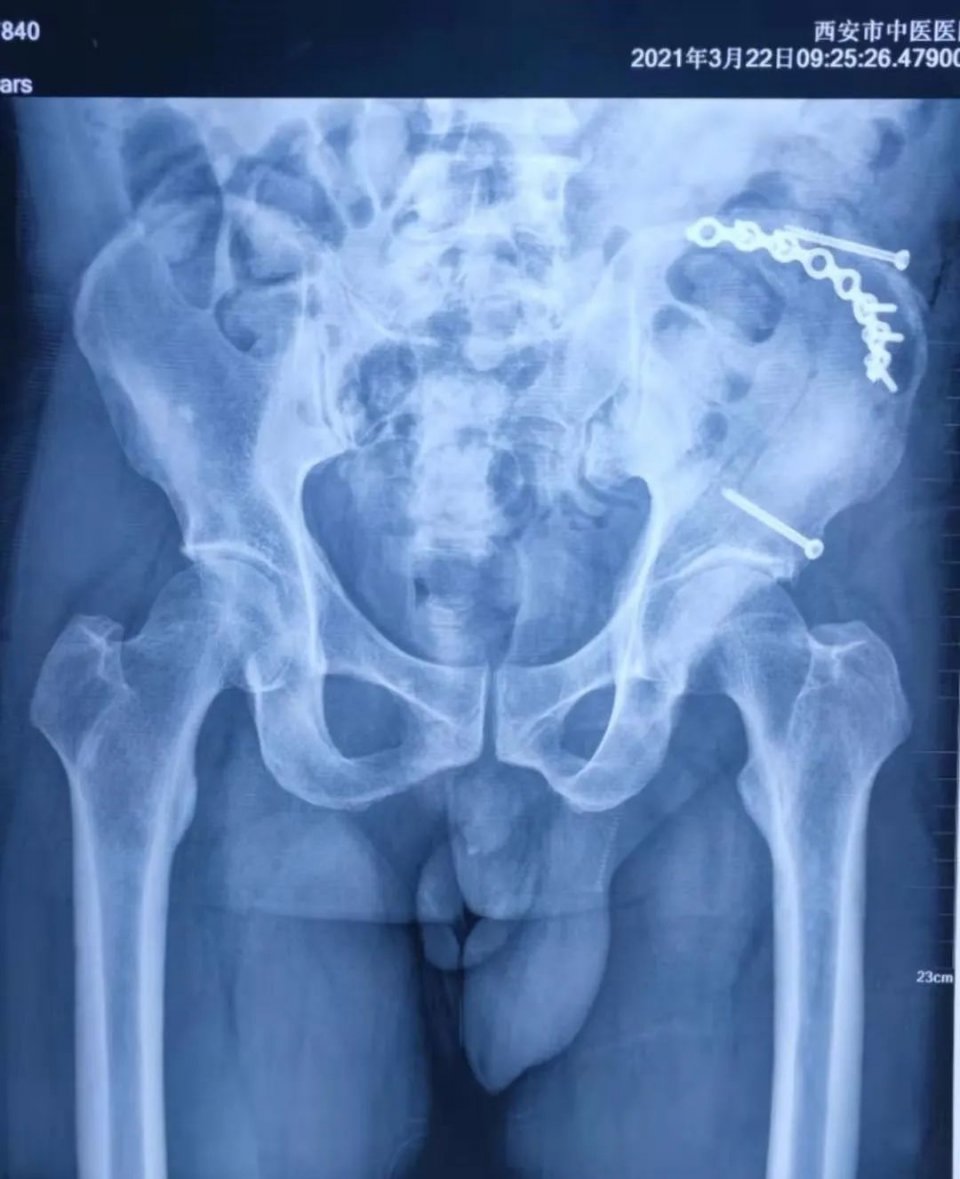

CT检查结果显示,老靳左侧髂骨翼、髋臼及耻骨上支骨折,断端错位,周围及腹膜后血肿已形成,临近器官受压移位;腹腔、盆腔有积血,双侧胸腔积血,肺有挫裂伤。

值得一提的是,老靳的骨折内固定手术方案引入了“微创”观念。老靳的骨折部位有两处,一处是位于骨盆上方的左侧髂骨翼,一处是位于骨盆侧面的髋臼及耻骨上支。

按照传统的术式,需在这两处分别切开皮肤、肌肉、骨膜,充分暴露骨折部分,合拢分离移位的骨折端,再置入钢板牢固固定。

范洪伟主任医师仔细阅片后,认为老金髋臼及耻骨上支处的骨折并无移位,通过经皮置入拉力螺钉即可牢固分离骨折端,这种术式切口小,能够减少手术损伤,利于术后快速恢复。

手术由范洪伟主任医师、宋铁兵副主任医师主刀,陶宝琛主治医师、张谨主治医师配合,复位髂骨翼处分离移位骨折端并以钢板固定,再以拉力螺钉固定髋臼处骨折,恢复骨折对位及骨盆稳定性,为老靳早期功能锻炼及负重生活争取条件。髋臼处的小切口仅有一1cm大小,可谓以“最小的代价”换取了“最优的固定”。